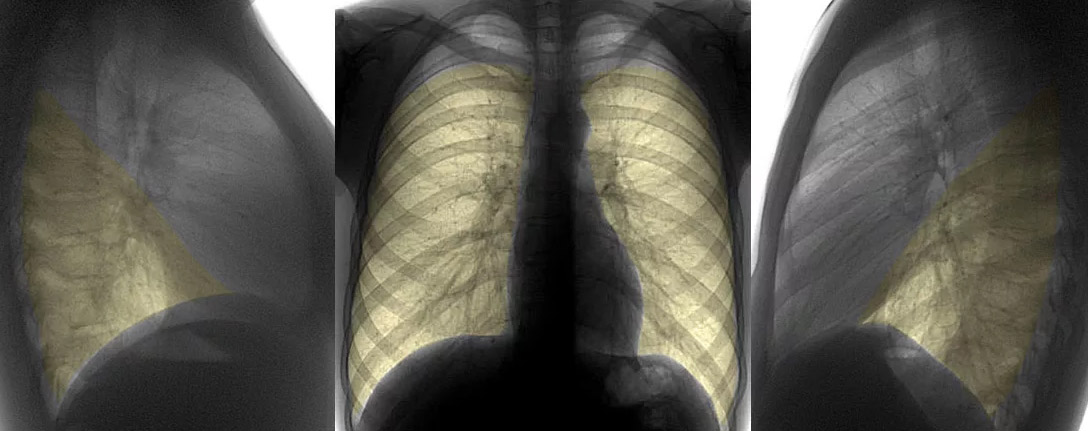

Рентгенодиагностика бронхопневмонии: Советы и примеры

Раздел: Альбом открытий